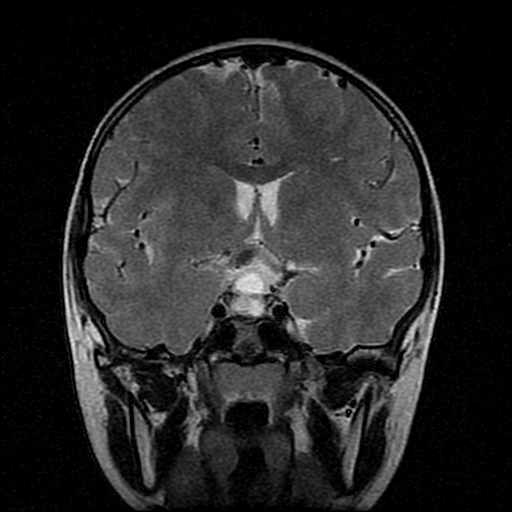

男性,12岁。反复头痛呕吐半月。脑积液无异常。病变部位ct值32hu,dwi无异常。

鞍上为主,累及鞍内,垂体受压位于鞍底。mri呈短t1、长t2信号,不太支持生殖细胞肿瘤,首考颅咽管瘤。

鞍内囊性占位性病变,t1wi、t2wi,均为高信号影。ct平扫为等密度。发病年龄较小。故首先考虑颅咽管瘤,可以做ct增强扫描